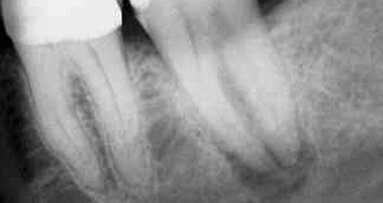

Des radiographies périapicales réalisées en routine n’ont pas été jugées nécessaires. C’est pourquoi, elles ont été prises 6 mois et 2 ans après la chirurgie, afin de vérifier le bon déroulement de l’ostéo-intégration. Un soin particulier y a été apporté afin d’utiliser la technique parallèle-perpendiculaire, c.-à-d., que le support du capteur a été placé parallèlement à l’axe des implants tandis que le tube à rayons X leur était perpendiculaire, de façon à garantir la meilleure projection pour chaque patient. Les radiographies ont été prises minutieusement afin de distinguer l’apex des implants et la face occlusale des couronnes, et permettre ainsi l’évaluation clinique du rapport racine/couronne. Outre le contrôle clinique, les radiographies ont été utilisées pour l’évaluation quantitative de la hauteur d’os, ce qui a été effectué par un seul examinateur (PZ) au moyen du logiciel ImageJ (NIH, États-Unis, version actuelle). Les images ont été mises à l’échelle sur la base de la hauteur connue du filetage des implants.27

L’évaluation radiologique de la hauteur d’os péri-implantaire a confirmé la stabilité remarquable de la hauteur osseuse, liée à l’utilisation de cette ligne d’im- plants (Fig. 1).27, 28, 29 La hauteur de l’os péri-implantaire s’est stabilisée à 0,9 mm ± 0,5 mm (moyenne ± écart-type) au-des- sous de la micro- anfractuosité, c.-à-d. au-dessous de la liai- son pilier-implant. Les implants utilisés avaient un col usiné de 1,0 mm et par conséquent, dans cette population de patients, la hauteur de l’os s’est également stabilisée au niveau de l’interface de la surface endo-osseuse modérément rugueuse.

Dans la cohorte susmentionnée, une patiente âgée de 74 ans présentait un édentement partiel de la région mandibulaire postérieure droite. Les dents avaient été extraites plus de 3 mois auparavant et trois implants ont donc été placés dans des sites cicatrisés. En raison de la distance au canal mandibulaire, la seconde prémolaire et la première molaire (positions 45 et 46) ont été remplacées avec des implants courts, afin d’éviter le risque de lésion du nerf. Les implants ont été recouverts avec des piliers de cicatrisation. Après deux mois de cicatrisation transgingivale (non enfouie) sans incident, les piliers de cicatrisation ont été retirés (Fig. 2). Cette image illustre également l’adaptation parfaite du tissu mou autour des implants. La prise d’une radiographie périapicale a confirmé l’absence de signes pathologiques (non-montrée). Une empreinte à ciel ouvert a été prise. L’armature a été vissée afin de garantir une adaptation passive, l’occlusion a été vérifiée et les couronnes prothétiques définitives (Fig. 3) ont été fabriquées et vissées dans les deux semaines qui ont suivi le retrait des piliers de cicatrisation. Une photographie intra-orale prise après deux années de fonctionnement présente l’issue très favorable et prévisible (Fig. 4).